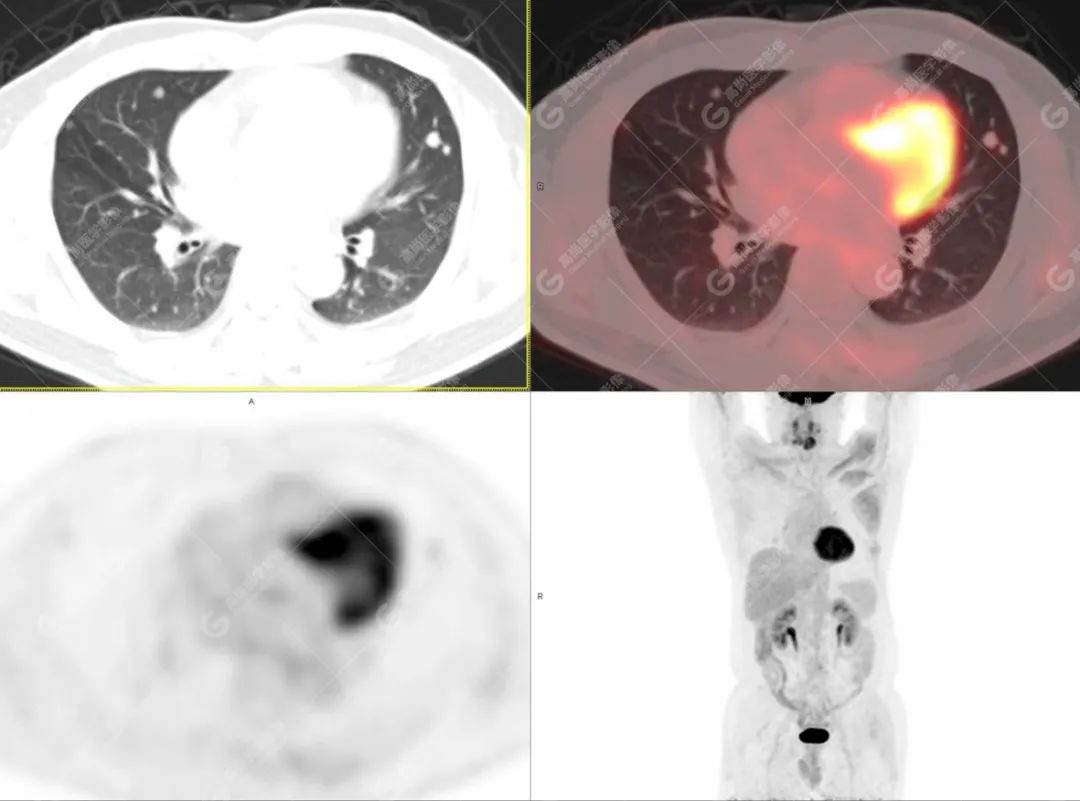

PET/CT影像图

图2

PET/CT检查

影像诊断: 1.舌体部左右侧软组织明显增厚,密度稍低,左侧为著,代谢异常增高, 考虑为舌癌,并口底受侵, 建议穿刺病理学检查明确。

2.双肺多发大小不等实性结节,部分代谢轻度增高, 考虑为转移瘤。

术后 病理: 口底癌; 考虑为口底癌侵犯舌神经致舌部麻木感。